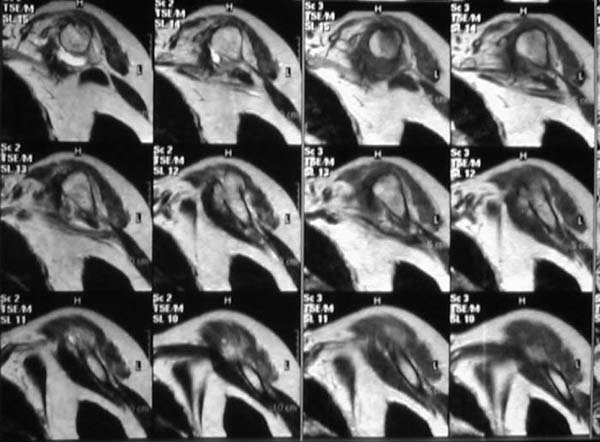

Уважаемые коллеги!Женщина, 60 лет. 3 недели назад упала с упором на отведенную левую руку. Почувствовала боль в левом плечевом суставе. За помощью не обращалась. 2 недели "мази и припарки". Затем - рентгенограмма (r1 и r2), жалобы на боли,ограничение движений...

Активное отведение 80 гр., при пальпации - головка плечевой кости безболезненно вправляется и тут же самостоятельно вывихивается. Наложена косыночная иммобилизация, рентгенография (r3) и МРТ.В нашем диагностическом центре МРТ исследование плечевого сустава выполнено впервые, опыта у нас маловато :(.Вопросы: уточнение диагноза? какие исследования провести? тактика лечения?

Из того, что видно на недостаточно качественно отсканированных МРТ - нижний подвывих плеча и синовиит. Непонятный очаг по заднему контуру головки плеча (то ли артефакт, то ли косой срез, проходящий между головкой и большим бугорком). Сухожилия вращательной манжетки выглядят целыми. Неправильная форма нижней части labrum glenoidale - разрыв ?

МРТ должен показать разрыв манжетки, но признаться я не большой эксперт по чтению МРТ сканов, хотя затемнение, отек мягких тканей по задней поверхности плеча видны Обычные рентгенограммы демонстрируют остеолизис в области большого бугорка.

1. На рентгене - нижний подвывих плеча и очаг остеолиза суставного бугорка с четкими контурами (вдавленный перелом на фоне остеопороза ? доброкачественная опухоль? аваскулярный некроз ? (хотя ни разу не слышал об аваскулярном некрозе плеча..)

Судя по снимкам, речь идTт о типичном случае Hill-Sachs Lesion. По этому поводу я позволю себе некоторый экскурс:

97 % всех вывихов плеча происходит по механизму комбинации отведения, разгибания и наружной ротации (А. Гринспан). В момент вывиха головка плеча ударяет о нижний край гленоида, что ведет к вдавленному или компрессионному перелому одной или обеих структур. Чаще всего, однако, повреждение возникает в задней латеральной области головки плечевой кости на переходе от головки к шейке. Этот диагноз можно выставить на основании рентгеновского снимка в переднезадней проекции с внутренней ротацией плеча. Несколько реже видно повреждение гленоида о передненижний перелом края. То, что мы называем Bankart Lesion. Это повреждение видно на ре. снимке в п.з. проекции при нейтральной позиции плеча. Разумеется хрящевые и мягкотканные повреждения (в смысле Банкарт) мы увидим лучше всего на ЯМР.

Учитывая описанную клинику, речь идTт о комбинации патологии. К сожалению, учитывая качество снимков NMR, я не могу провести достаточно точную верификацию состояния нижнего края гленоида, что впрочем, не меняет рекомендации. Для определения состояния РМ и дополнить исследование УЗИ мягких тканей плеча. В опытных руках достаточно информативное и дешевое исследование.